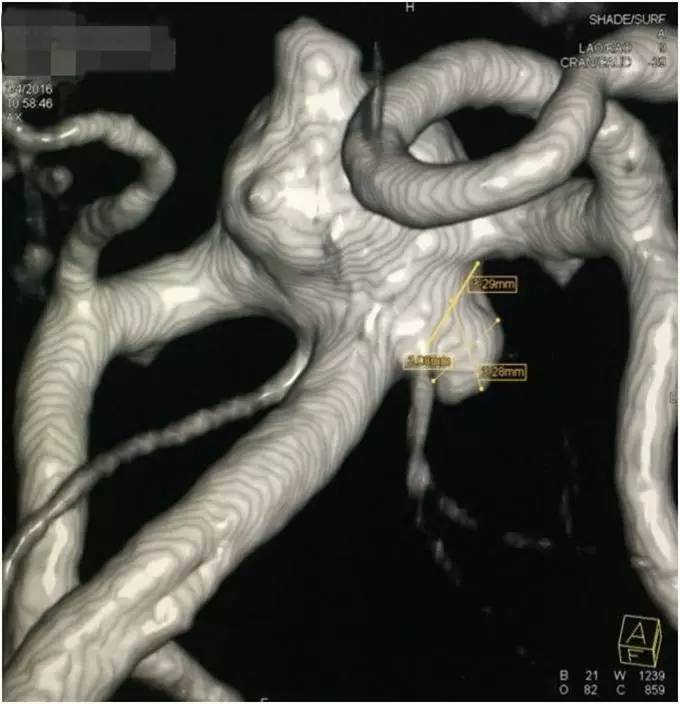

▼左小脑上动脉瘤测量